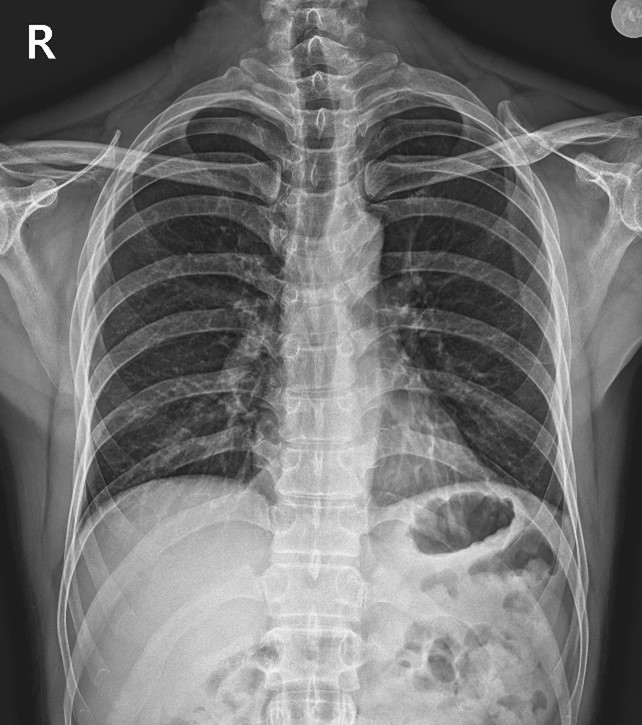

X-ray를 다시 찍고, 환자분이 가져오신

MRI와 비교해가며 세밀하게 체크했어요.

그리고 초음파로 갈비뼈 사이 부위를 확인했죠.

그리고 저는 진단을 내렸습니다.

늑간신경통이라고요.

그림6.jpg

<Fig 1. X-Ray 영상>